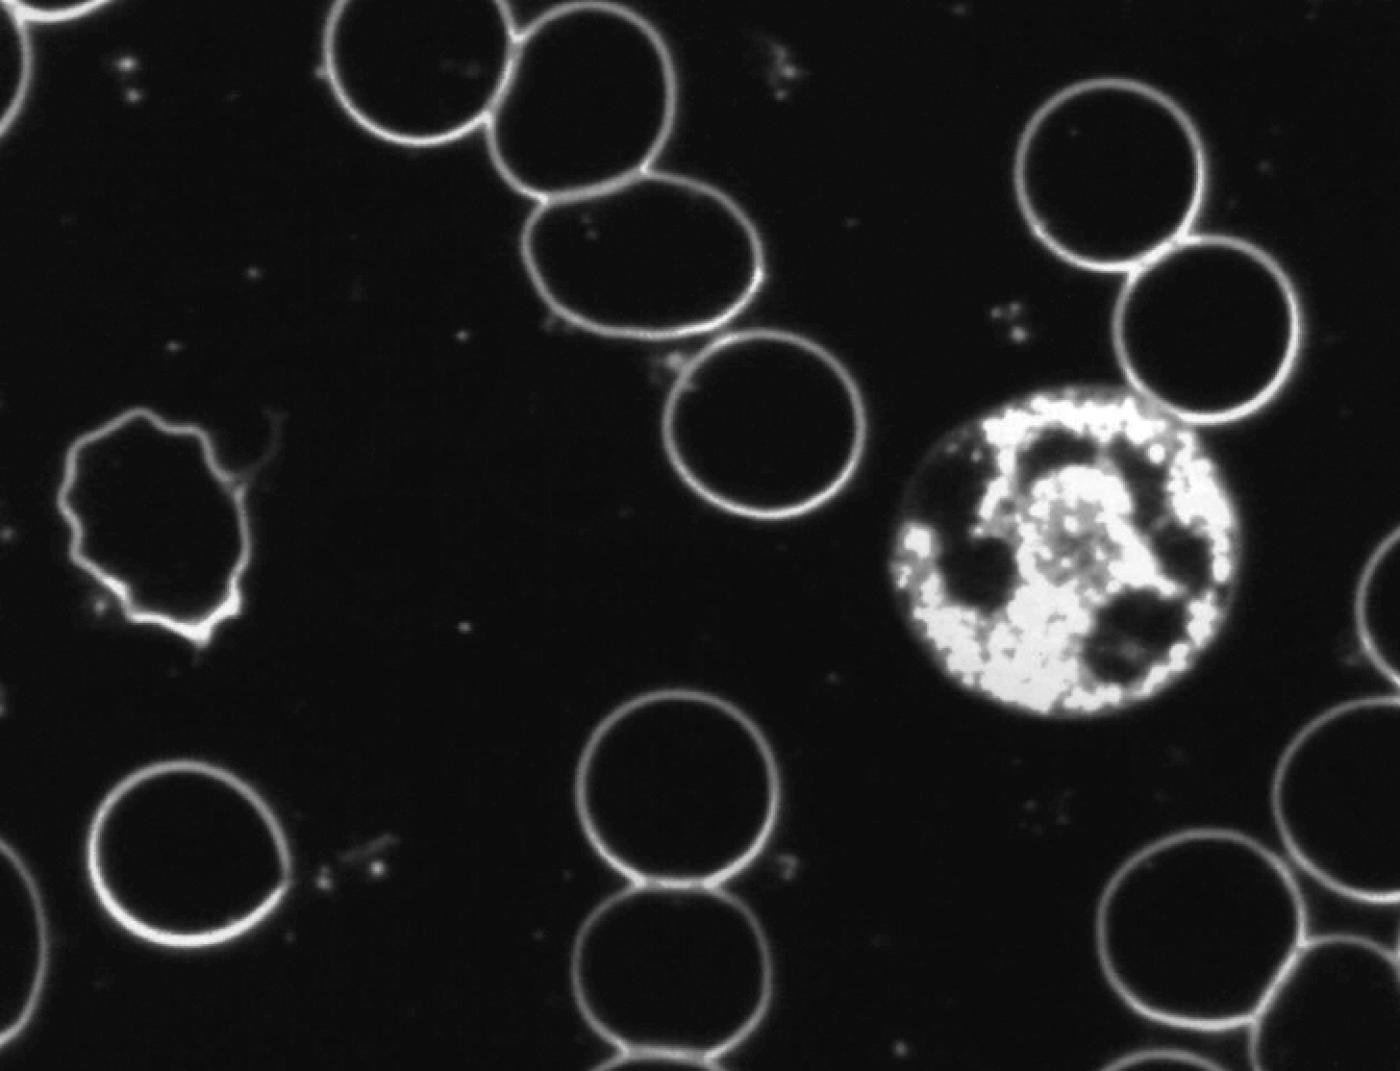

Zie ook onderstaande foto’s met een karakteristiek beeld van vóór en na de neutralisatie met Benzoliet.

Levend bloedbeeld

vóór neutralisatie met Benzoliet

De veranderingen die we hebben geconstateerd in met name de witte cellen na blootstelling aan technische en geopathische verstorende subtiele energieën, waren:

- afname van beweeglijkheid van de cel

- het aannemen van de bolvorm

- afgenomen en op een plek geconcentreerde cytoplasmatische activiteit

Onze conclusie is dat de effectiviteit van het immuunsysteem onder invloed van de subtiele verstorende energieën vermindert.